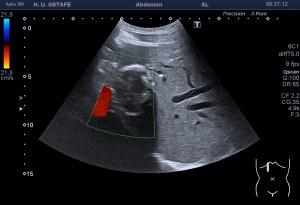

En esta última imagen te muestro la angiogénesis o neovascularización. Existe un aumento de aporte sanguíneo para reparar aquel tejido que está dañado. Esta angiogénesis o aumento de vascularización y por tanto Doppler podría ser secundario a un proceso de reparación mal gestionado por el tejido. Esta angiogénesis también podría estar en relación con aumentos del dolor en la zona y no significa que la patología cure antes. Gracias Javier. Gracias Amigo.